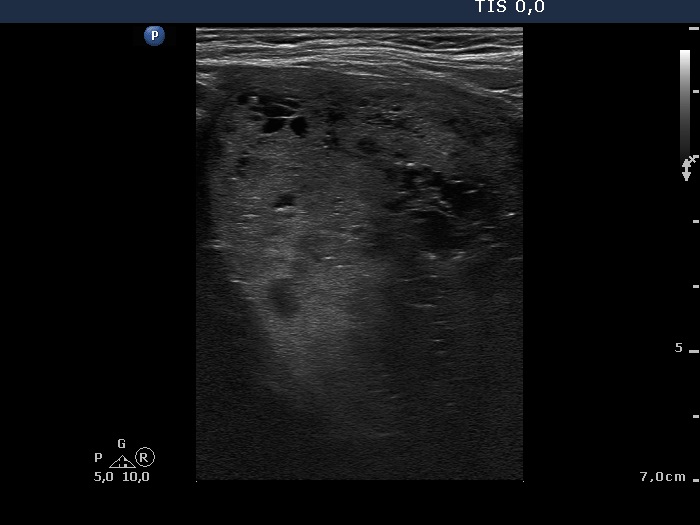

Benign hyperplastic nodule (histological diagnosis) - case 2 |

The bright granules lack the dorsal narrowing tail and there are no coexisting similarly bright lines, therefore these granules correspond to punctate echogenic foci.